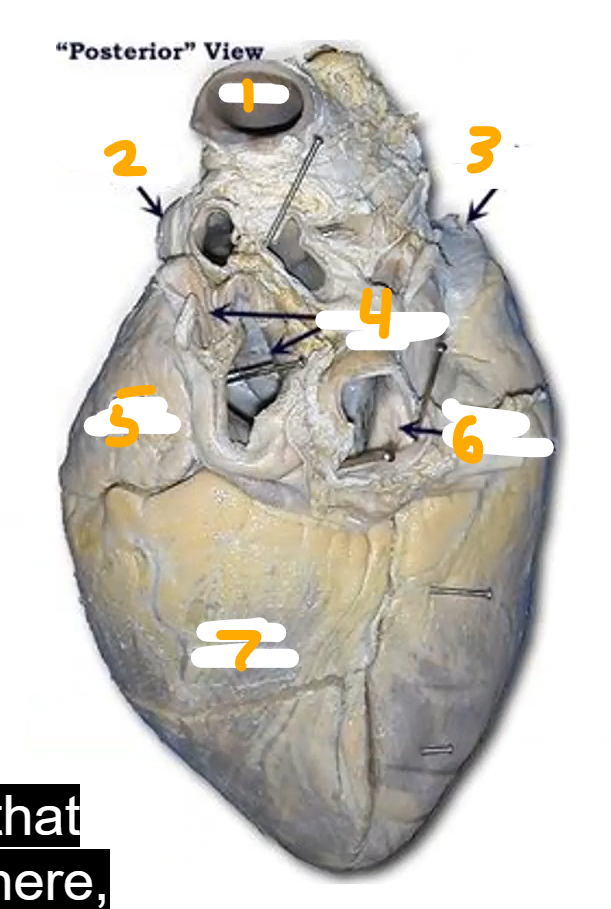

Where is the auricle

Aorta

2. Pulmonary Heart

3. Superior Vena Cava

4. Pulmonary Vein

5. Left auricle

6. Inferior vena cava

7. Left ventricle

Name (top left shows orientation)

Aorta

2. left auricle

3. left atriumright ventricle

interventricular septum

left ventricle